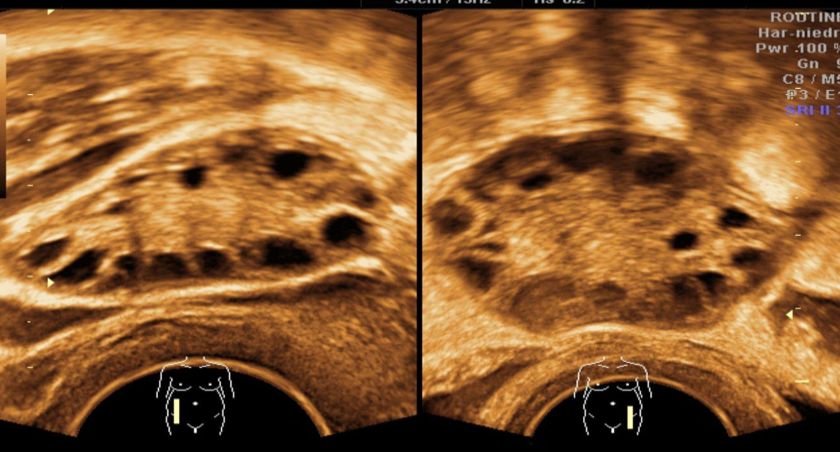

A. Imaging study Transvaginal ultrasound of the right and left ovary: B. Describe the abnormality both ovaries contain multiple anechoic cysts. There is a relative increase of stromal tissue and capsule thickness with increased ovarian size C. What is the most likely diagnosis polycystic ovary syndrome.